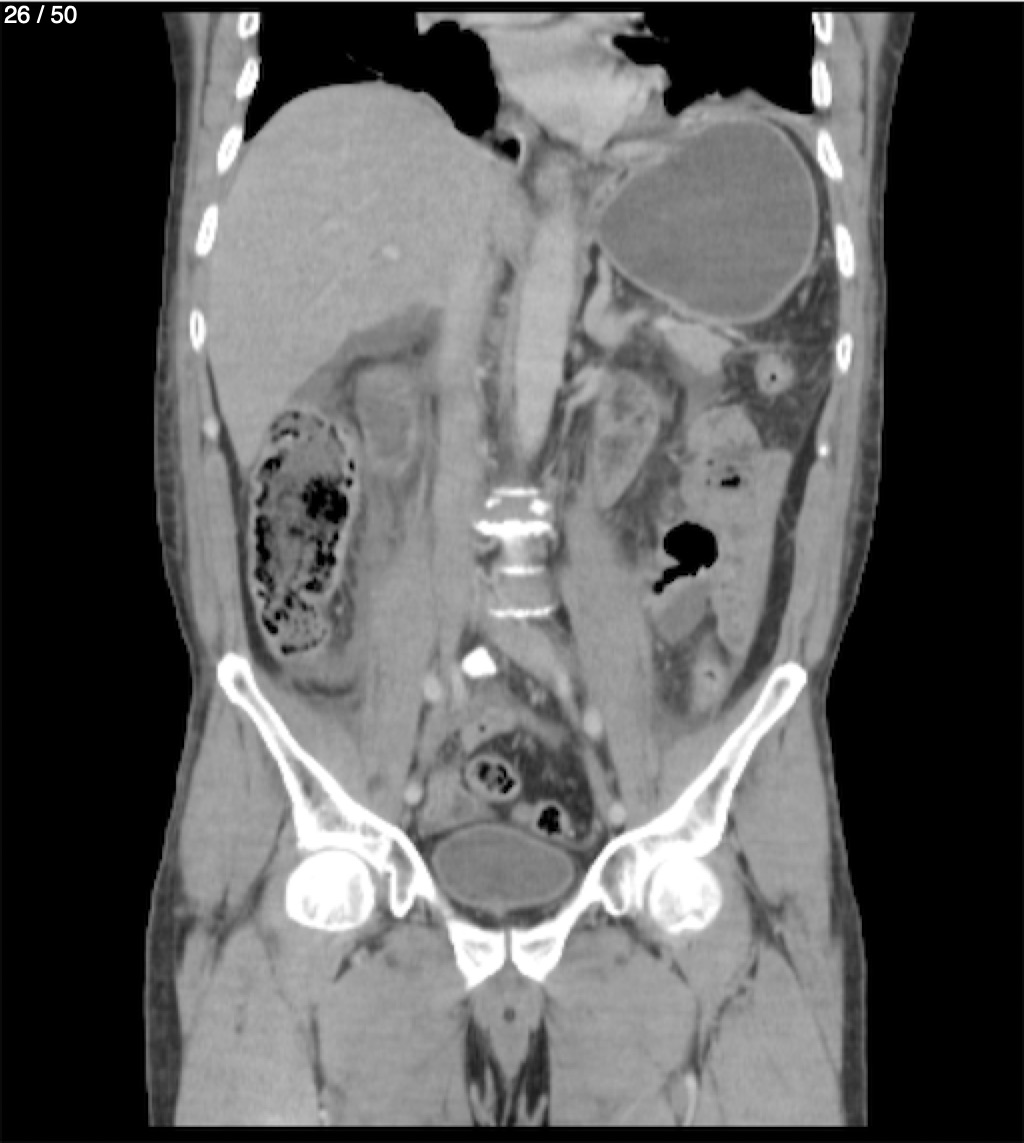

Alonso Victorio Ruiz 62A - T.C Abdomen Syc